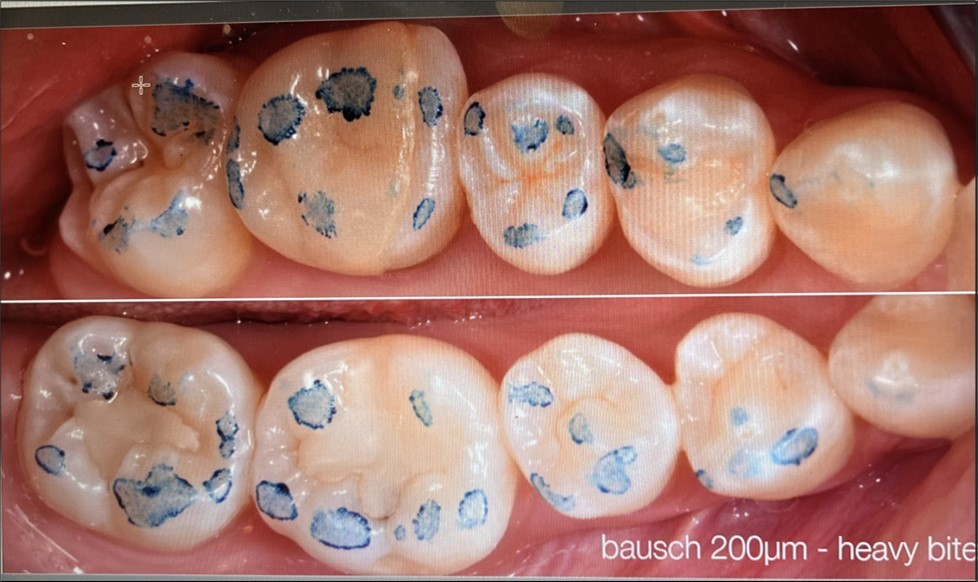

This observational study compares four clinically used methods for recording occlusal contacts. Recordings were made using each of four different methods on the same subject who volunteered participation. All recordings were made in office by one clinician (CS) during the same time period. A clinical subject with few restorations was selected and the subject agreed to the procedure along with the right to publish the results. There are no quantitative measurements. Ankylosis is a factor that was not addressed. The recording indicator systems evaluated were: 1. Accufilm (Parkell, Brentwood NY. USA). 2. Blue paper (Bausch, Nashua NH. USA), 3. Primescan (Densply/Serona, Waltham MA. USA), 4. PMscan (Mco, Boston MA. USA). In all procedures the subject was advised on how to close and the procedure was repeated. The subject made one hard closure into or onto the marking surface and the results were recorded and are displayed in (Figure 1) (Figure 2, Figure 3, Figure 4 )

Material 2: Blue marking paper {Figure 2} is thick (200 microns) and records high points. Variations in markings occurred. Biting light missed some markings and biting hard made too many. Intensity could not be measured. Records could not be stored.